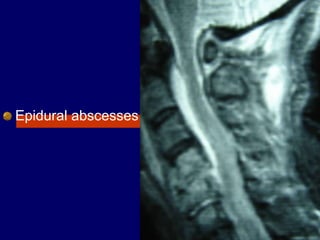

Epidural abscesses

Of the spinal column is

a rare but potentially

devastating disease.